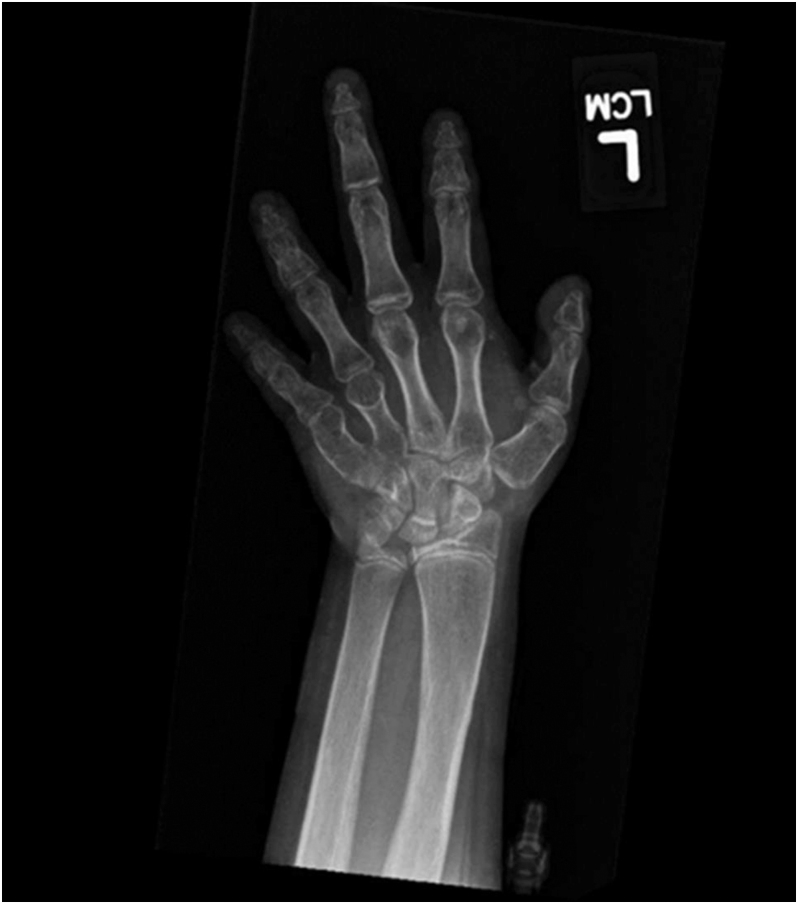

Abstract Image